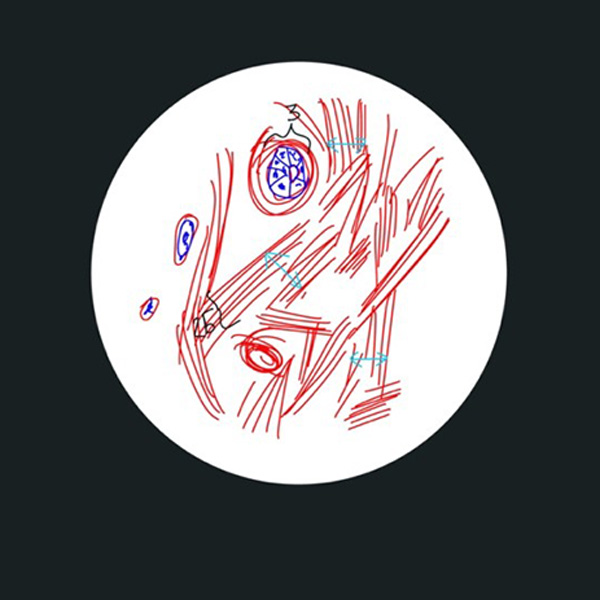

Рис. 2. Виды соединительной ткани в панч-биоптате после курса сеансов воздействия, окраска гематоксилин+эозин: кровеносные сосуды-капилляры (3), строго ориентированные пучки волокон (2Б) в стромальных трабекулах и большое количество активных фибробластов (2А). Голубыми стрелками указаны длины просвета сосудов.

Косвенно это подтверждается второй группой зафиксированных изменений на фоне применения аппарата Beautylizer (RSL-скульптурирование*): увеличении просвета сосудов микроциркуляторного русла на единицу площади зоны, что свидетельствует об активации не только функциональной части микроциркуляторного русла, но и стимуляции работы как коллатерального кровообращения, так и основного. Активное кровоснабжение позволяет не только снизить задержку жидкости в тканях и формирование отеков, но и простимулировать активную работу клеток, продуцирующих полезные белковые компоненты соединительной ткани3.

Третьей группой обнаруженных изменений является увеличение междольковых перемычек4, что, вероятно, указывает на снижение фиброзирования данных септ. Помимо функционального значения, эта группа несет ярко выраженный визуальный эффект в виде уменьшения выраженности «апельсиновой корки».